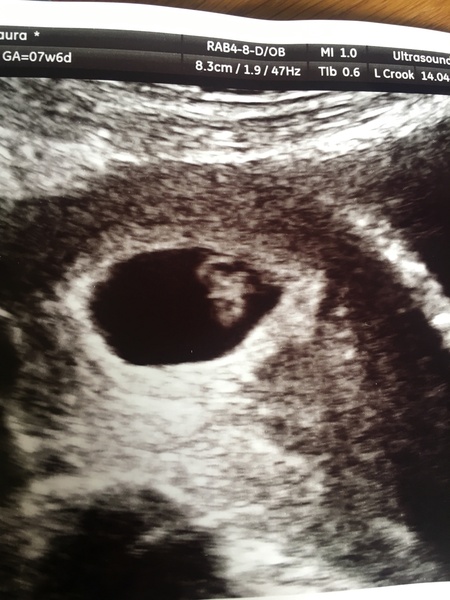

Bora88 · 17/04/2018 16:43

I have just had a private viability scan on Saturday & I was exactly 7 weeks. They could see a yolk sac, a fetal pole & detected a heart beat. All crazy considering the ‘baby’ was less than 1cm in size. I have attached the picture. Me & OH have both noticed it looks like a witch & now we have seen it we can’t unsee it lol